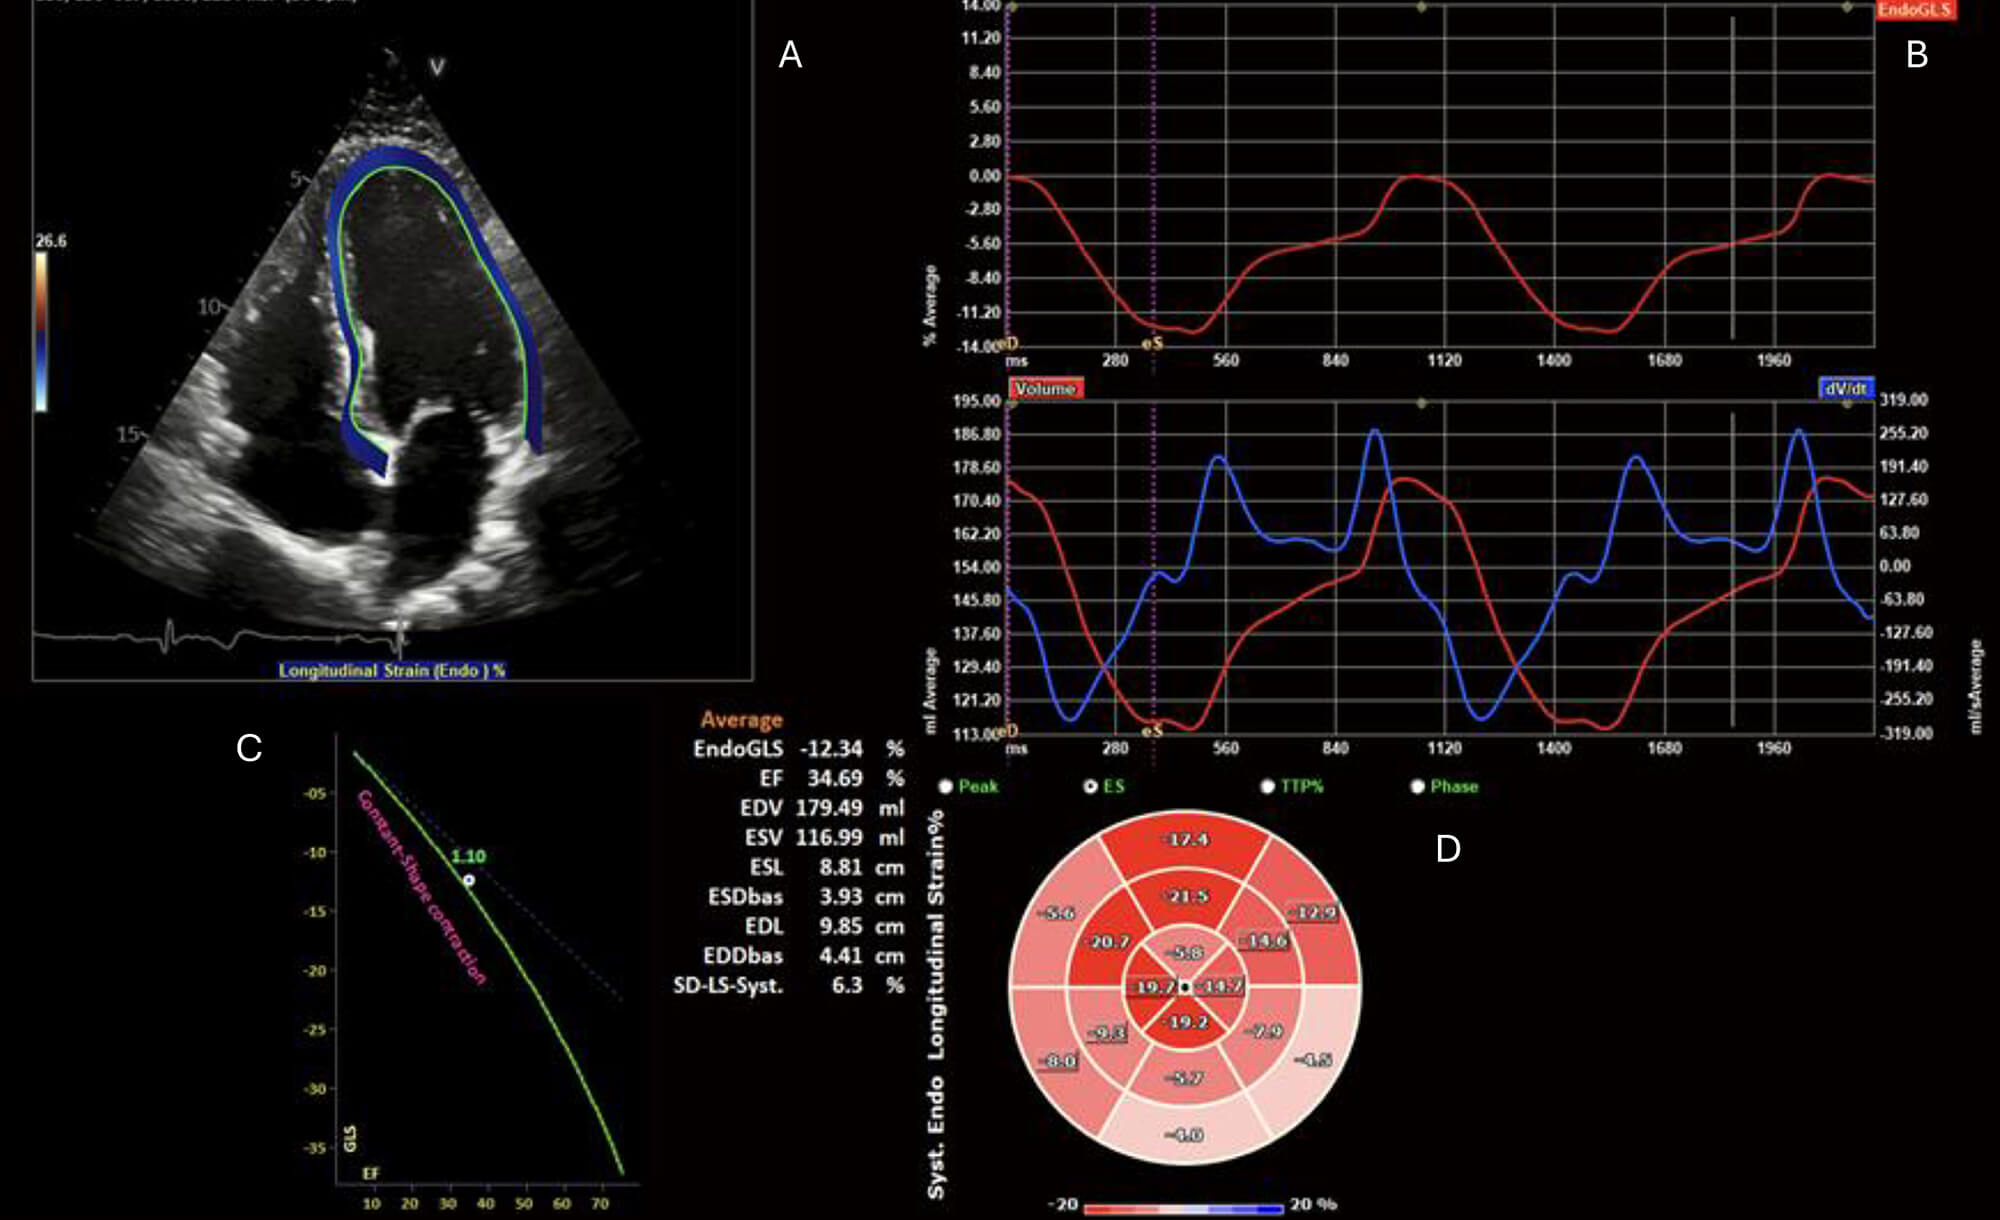

Contemporary methods, such as strain analysis (Fig. 1), which measure the displacement of tissue (pixels) and thus strain over the course of the cardiac cycle, can be helpful in cases of myocarditis owing to the inability of echocardiography to accurately characterise myocardial inflammation. Global longitudinal and radial strain correspond to areas of myocardial inflammation on biopsy [20] and, in both 2D and 3D imaging, have been correlated with regional changes of inflammation and late gadolinium enhancement (LGE) on CMR [21, 22].

Fig. 1.

Echocardiogram with endocardial speckle tracking and global longitudinal strain analysis. (A) 2D apical 4-chamber view with endocardial border speckle-tracking. (B) Upper: EndoGLS over time (ms), and lower: LV volume curve (red) and dV/dt (blue) over time (ms). (C) Reference plot for global longitudinal strain (GLS) vs LVEF. (D) 16-segment polar map if segmental EndoGLS demonstrating regional reduction in longitudinal strain, particularly affecting the basal inferior and inferolateral segments. ES, End-Systole; TTP, Time to Peak; EndoGLS, endocardial global longitudinal strain; EF, ejection fraction; EDV, End-Diastolic Volume; ESV, End-Systolic Volume; ESL, End-Systolic Length; ESDbas, End-Systolic Diameter, basal; EDL, End-Diastolic Length; EDDbas, End-Diastolic Diameter, basal; SD-LS-Syst., Standard Deviation of Longitudinal Strain during Systole.